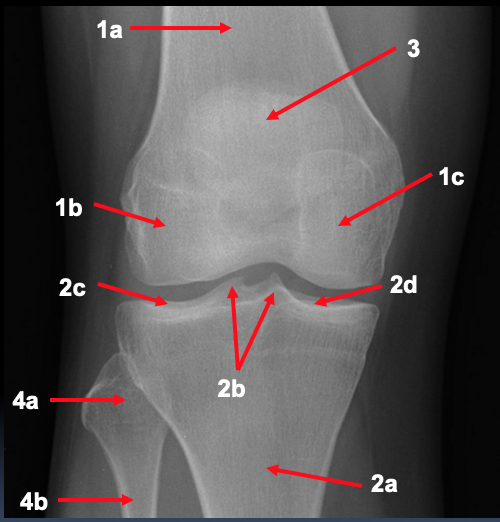

What is shown by 1 on the AP right knee radiograph?

1. femur

a. distal shaft

b. lateral condyle

c. medial condyle

What is shown by 2 on the AP right knee radiograph?

2. tibia

a. proximal shaft

b. spines/intercondylar eminence

c. lateral plateau

d. medial plateau

What is shown by 3 and 4 on the AP right knee radiograph?

3. patella

4. fibula

a. head

b. proximal shaft